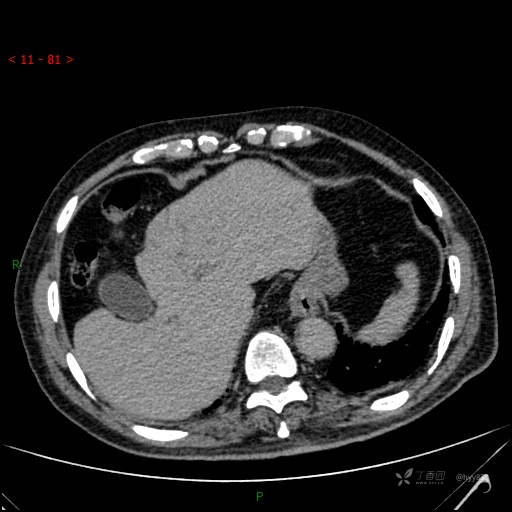

静脉期

img